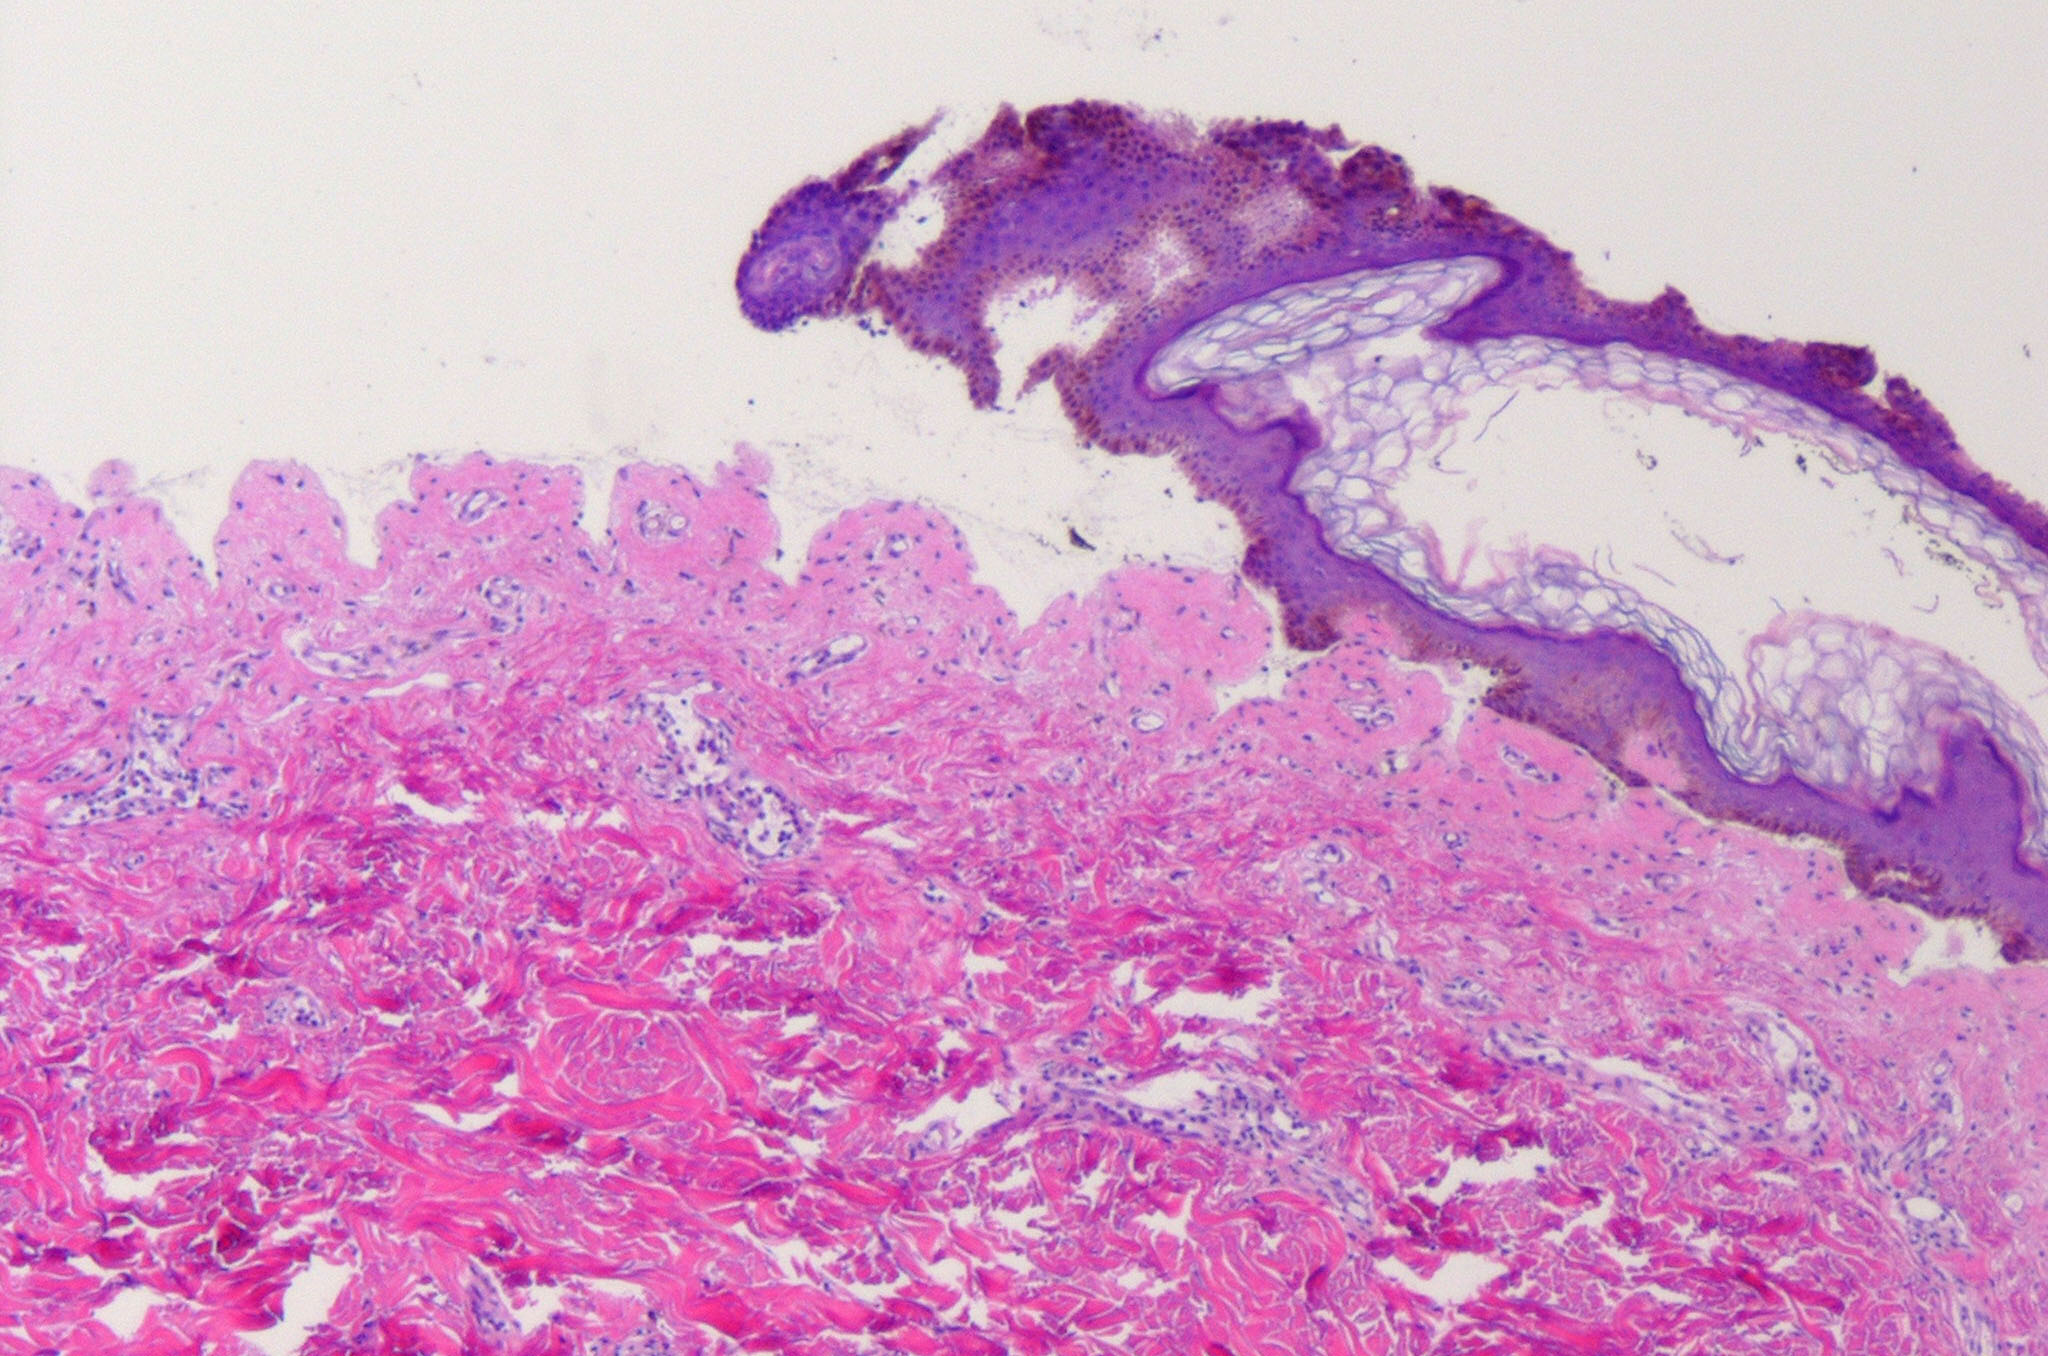

Histopathology.

In early lesions, papillary dermal edema in combination with a cell-poor or cell-rich perivascular lymphocytic and eosinophilic infiltrate is present. The blister arises at the dermal-epidermal junction . In the cell-rich pattern, which correlates clinically with blisters arising on erythematous skin , eosinophilic papillary abscesses may develop with numerous perivascular and interstitial eosinophils intermingled with lymphocytes and neutrophils in the superficial and deep dermis. Early lesions may have the histologic features of eosinophilic cellulitis (Well’s syndrome). Eosinophilic spongiosis may occur. The cell-poor pattem is observed

when blisters develop on relatively normal skin , in which there is usually a scant perivascular lymphocytic infiltrate with few eosinophils, some scattered throughout the dermis and others near the epidermis. The blister contains few inflammatory cells. Epithelial migration and regeneration may result in an intraepidermal split in older blisters. Similar to pemphigus vegetans, a hyperplasia of the epidermis, subepidermal bullae, and accumulations of eosinophils and lymphocytes may be seen.